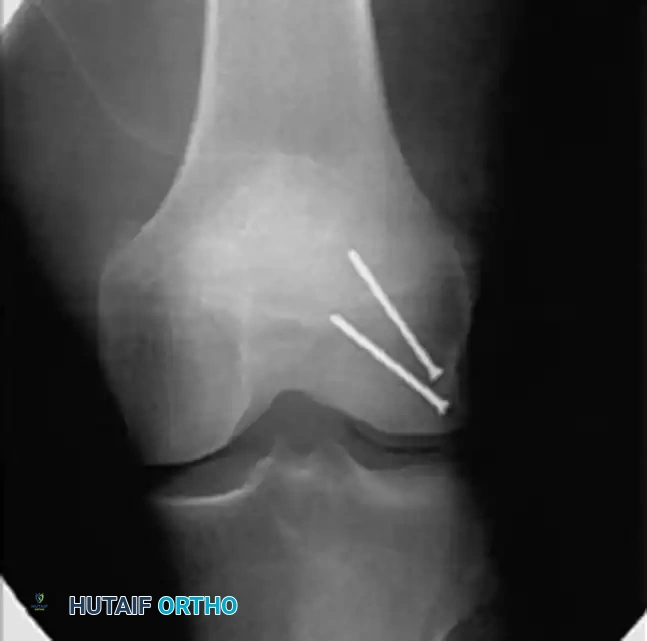

Intraoperative posteroanterior radiograph demonstrating precise lag screw fixation of a distal femoral condylar fracture, achieving absolute stability of the articular block.